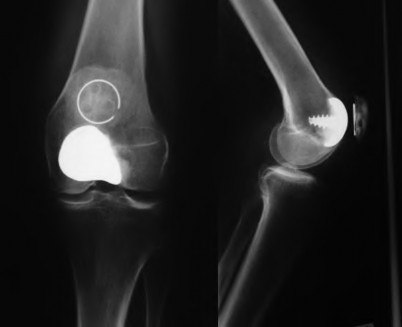

A patient presents with persistent anterior knee pain and a 'clunking' sensation 1 year following a primary total knee arthroplasty. On physical exam, the patella tracks laterally and there is tenderness over the lateral retinaculum. Radiographs and CT scan are obtained. Which of the following component malpositions is most likely responsible for lateral patellar maltracking?

Explanation